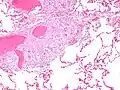

Granulomatous inflammation is characterized primarily by the accumulation of macrophages and activated T-lymphocytes, with increased production of key inflammatory mediators, TNF, IFN-γ, IL-2, IL-8, IL-10, IL-12, IL-18, IL-23 and TGF-β, indicative of a Th1-mediated immune response.[80][87] Sarcoidosis has paradoxical effects on inflammatory processes; it is characterized by increased macrophage and CD4 helper T-cell activation, resulting in accelerated inflammation, but immune response to antigen challenges such as tuberculin is suppressed. This paradoxic state of simultaneous hyper- and hypoactivity is suggestive of a state of anergy. The anergy may also be responsible for the increased risk of infections and cancer.

The regulatory T-lymphocytes in the periphery of sarcoid granulomas appear to suppress IL-2 secretion, which is hypothesized to cause the state of anergy by preventing antigen-specific memory responses.[88] Schaumann bodies seen in sarcoidosis are calcium and protein inclusions inside of Langhans giant cells as part of a granuloma. Sarcoidosis is characterized by the formation of non-caseous epithelioid cell granulomas in various organs and tissues.[89]